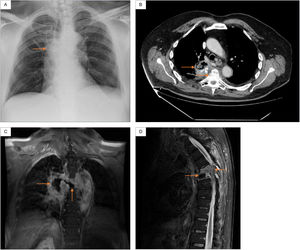

Physical examination was notable for crackles on auscultation in the upper and middle fields of the right lung, as well as spastic paraparesis with normal rectal tone. Blood test showed increased C-reactive protein 15mg/dL (reference range 0.5–1). Chest X-ray showed right paratracheal infiltrates (Fig. 1A). Chest CT showed cavitating right lung consolidation and crush located at T5-T6 (Fig. 1B). Thoracic spine MRI showed lung-spinal fistula and signs suggestive of spondylodiscitis (Fig. 1C and D).

(A) Chest X-ray: right paratracheal infiltrates. (B) Chest CT: right lung consolidation occupying the azygo-esophageal recess, with aire-fluid level and calcium deposits, as well as a marked crush and destructuring located at the T5-T6. (C) Thoracic spine MRI (coronal): central necrotic-cystic zone occupyping the disc space of the T5-T6 and fistulous communication with the adjacent right lung injury. (D) Thoracic spine MRI (sagittal): diffuse gadolinium enhancement and kyphotic deformity with canal stenosis located at the T5-T6.